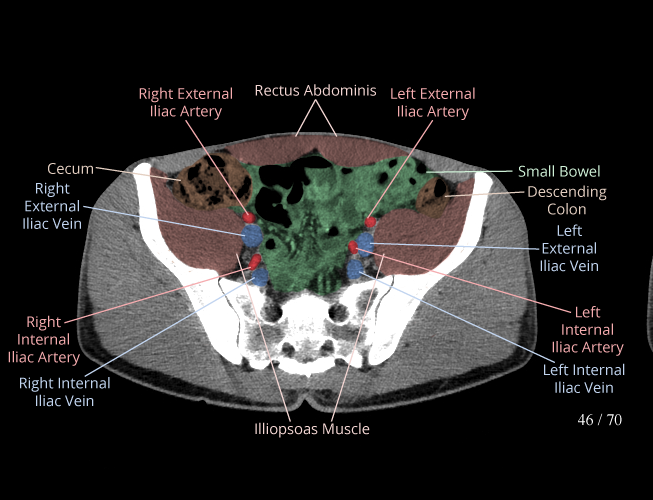

Pelvis

Covers pelvic MRI anatomy.